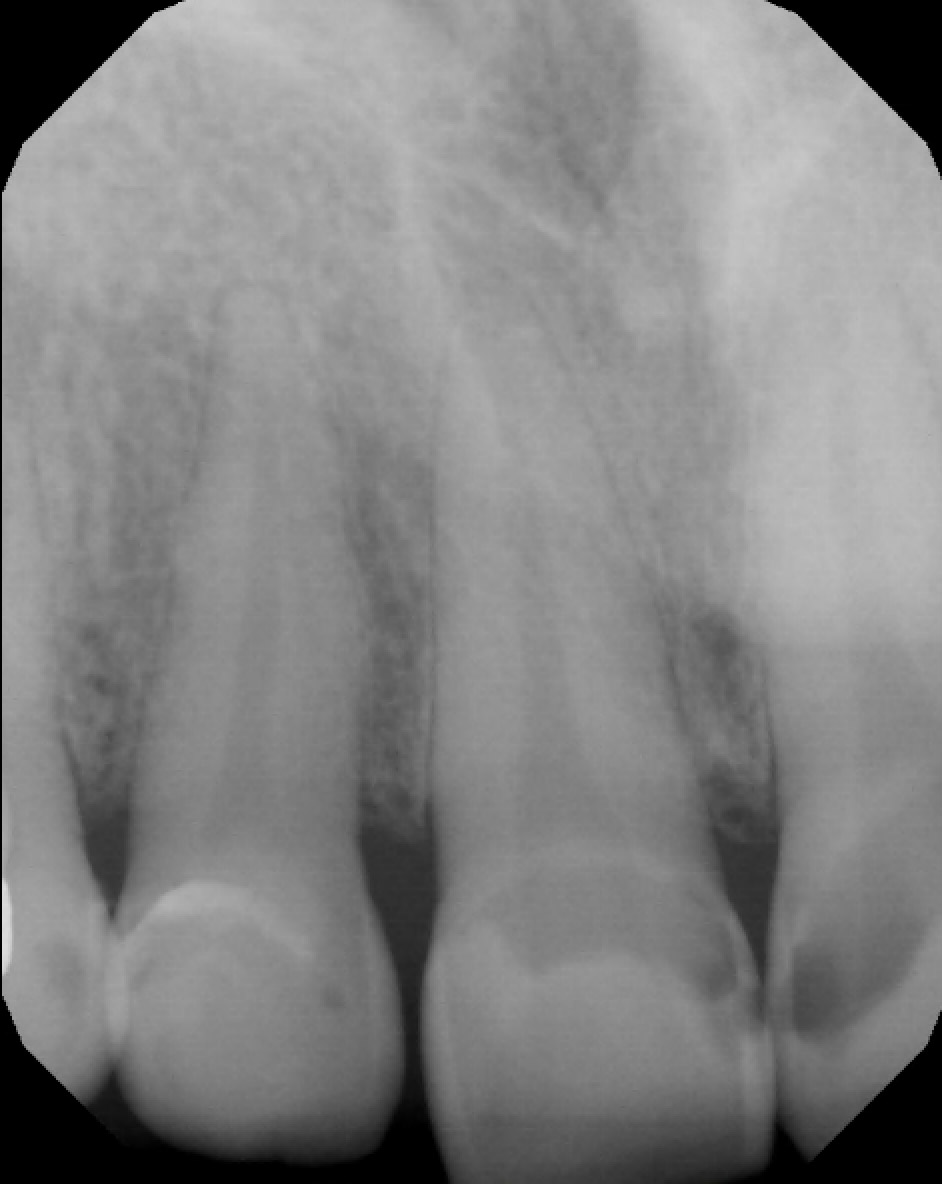

Note: 11 (US # 8) and 21 (US # 9) have caries into the pulp and peri apical lesions

• Periapical lesion on 11 (US # 8) and 21 (US # 9): correlates with the clinical finding of eroded teeth down to the dentin (almost the dentino-pulp junction)

• Conclusion: The radiolucencies seen at the apex of 11 and 21 (US # 8 and 9) were not periapical lesions. I retook a PA with a different angle (see next slide)

• Additional radiographs

Note: No periapical lesion is noted on 11 and 21 (US # 8 and 9).